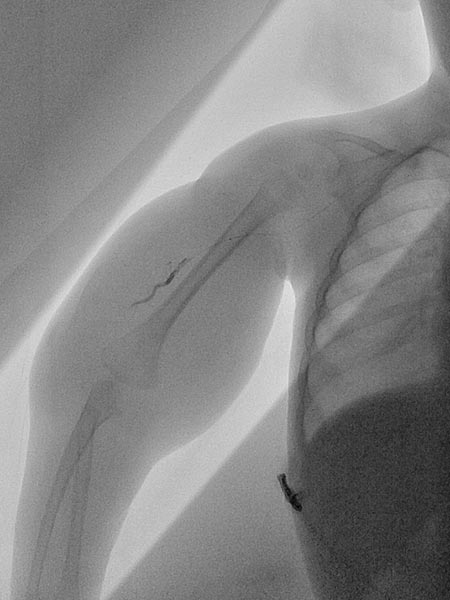

Digitale Subtraktionsangiographie links über die Arteria brachialis und rechts über den Mikrokatheter, welcher in der hypertrophierten Feederarterie am rechten Oberarm platziert wurde.